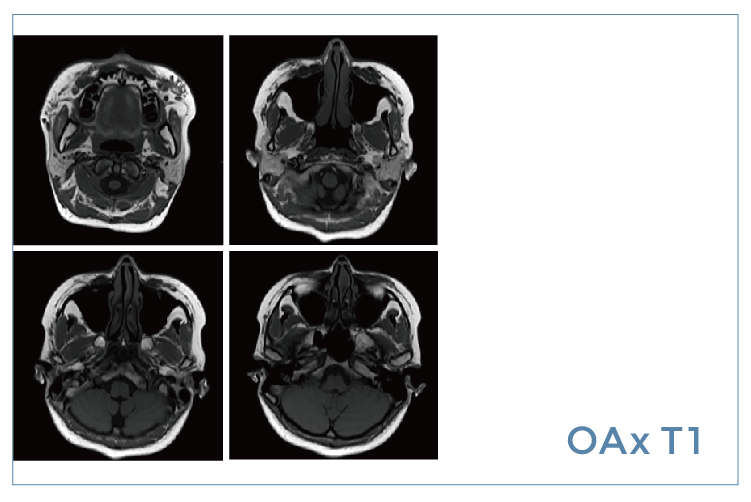

【朗润影像档案】20200522磁共振影像病例结果讨论

【朗润影像档案】磁共振影像病例分享(编号20200522)

【朗润影像档案】20200515磁共振影像病例结果讨论

【朗润影像档案】磁共振影像病例分享(编号20200515)

【朗润影像档案】20200424磁共振影像病例结果讨论

【朗润影像档案】磁共振影像病例分享(编号20200424)

【朗润影像档案】20200417磁共振影像病例结果讨论

【朗润影像档案】磁共振影像病例分享(编号20200417)

【朗润影像档案】20200410磁共振影像病例结果讨论

【朗润影像档案】磁共振影像病例分享(编号20200410)

【朗润影像档案】20200403磁共振影像病例结果讨论

【朗润影像档案】磁共振影像病例分享(编号20200403)